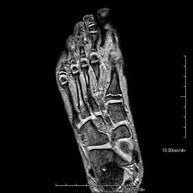

Exploració per estudiar aquesta articulació i les lesions freqüents de lligaments (esquinços), així com l'afectació d'altres estructures, com el cartílag o l'os. També és de gran utilitat per diagnosticar alteracions al tendó d'Aquil·les (tendinitis o trencaments). La durada aproximada és de 20 minuts. No utilitza radiació ionitzant. - RM de Peu

Exploració per a l'estudi de lesions en tendons, músculs i petites articulacions. Permet valorar amb eficàcia les lesions al cartílag. També és de molta utilitat per completar l'exploració ecogràfica prèvia. No empra radiació ionitzant. Té una durada aproximada de 20 minuts. - Artro-RM Hombro